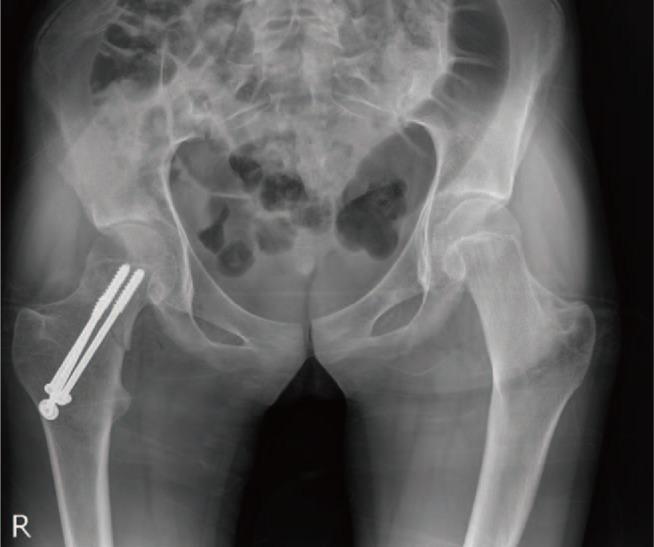

一名年轻马凡综合征患者的股骨颈骨折

Femur Neck Fracture in a Young Marfan Syndrome Patient.

Marfan syndrome is an autosomal dominant and could decrease bone mineral density. So patients with Marfan syndrome could vulnerable to trauma in old ages. We present the first report, to the best of our knowledge, of a rare fracture of the femoral neck with a minor traumatic history in a juvenile Marfan syndrome patient whose physis is still open. Although the patient is young, her bone mineral density was low and the geometry of femur is changed like old ages. The femur neck fracture in children is very rare and only caused by high energy trauma, we concluded that the Marfan syndrome makes the bone weaker in young age and preventative medications to avoid fractures in younger Marfan syndrome patients are necessary in early ages.

摘要

马凡综合征是一种常染色体显性疾病,可导致骨密度降低。因此,马凡综合征患者在老年时易受创伤。据我们所知,我们首次报告了一名骨骺仍未闭合的青少年马凡综合征患者,其股骨颈发生罕见骨折,且外伤史轻微。尽管患者年轻,但她的骨密度较低,股骨形态已如老年人般改变。儿童股骨颈骨折非常罕见,通常仅由高能量创伤引起,我们得出结论,马凡综合征会使年轻人的骨骼更脆弱,因此有必要在早期对年轻的马凡综合征患者采取预防措施以避免骨折。